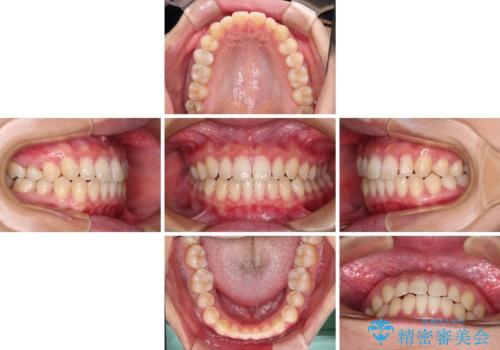

隙間だらけの歯列 インビザラインで改善

- 前歯の上下スペースと前歯の隙間を気にして来院された患者様です。

飲み込みや話をするときに舌を突出させる癖が強くあり、それが原因でスペースが空いていました。

舌癖を改善するためのトレーニングを行いながら、インビザラインにより上下の前歯の隙間を閉じていくこととしました。